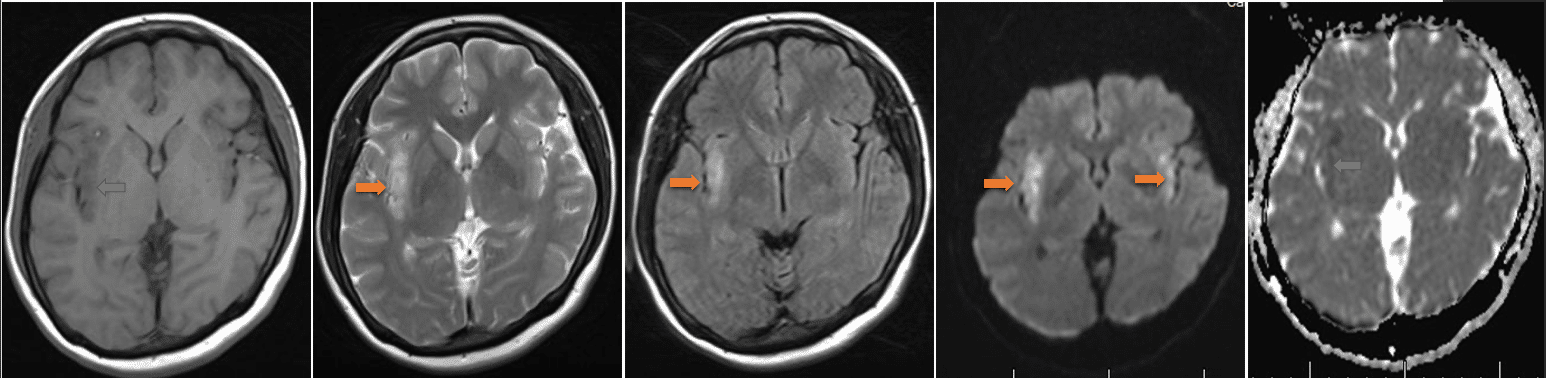

头MR(2925-12-12 我院) :序列依次为T1、T2、Flair、DWI及ADC,双侧导叶脑皮层及皮层下可见长T1、长T2、Flair高信号影,DWI呈高信号,ADC信号歼敌,右侧更为明显。 影像诊断 :双侧岛叶脑皮层及皮层下病变,考虑脑炎可能性大,请结合临床病史。